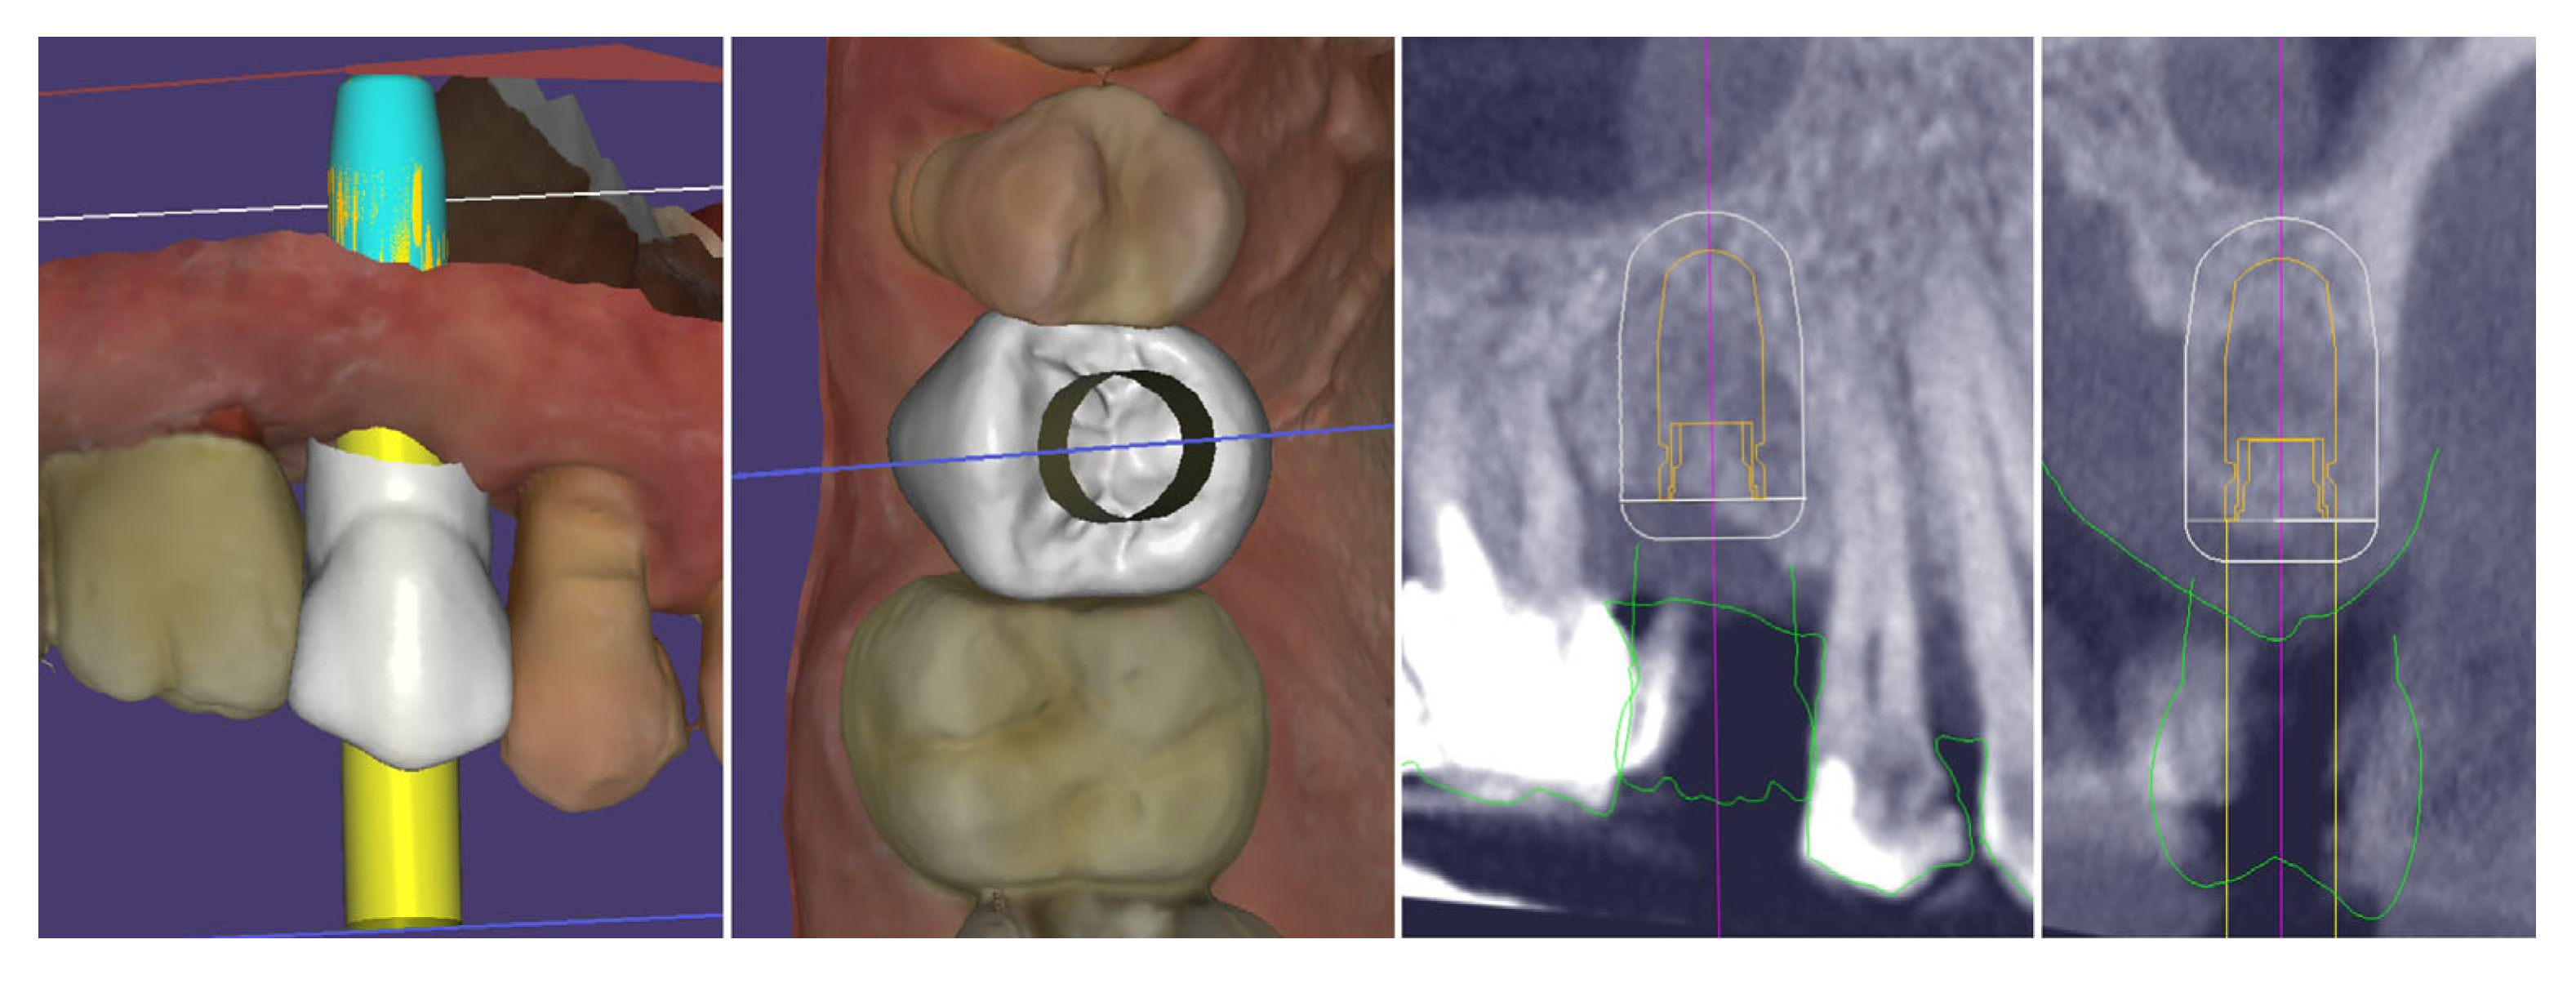

2. Materials and Methods—Clinical Case